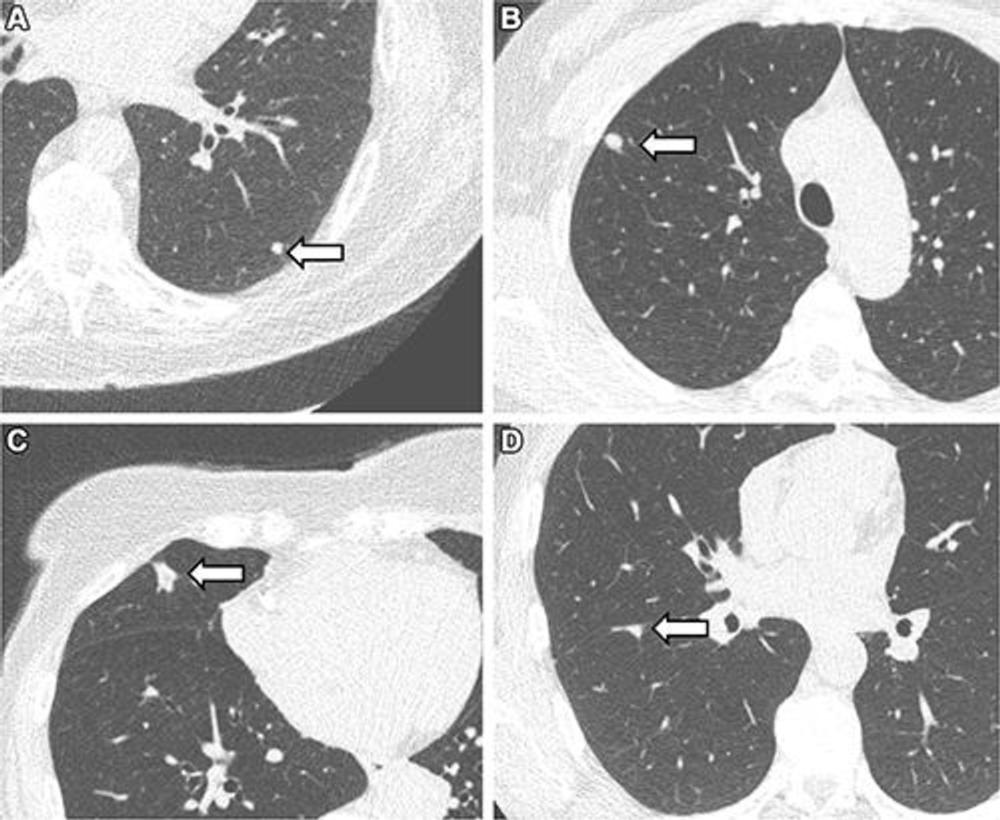

Figure 3. Representative chest low-dose CT images show lung nodules (arrows) and were included in the study. (A) A solid lung nodule, 82 mm3, in a 77-year-old male participant. (B) A clinically relevant nodule, 174 mm3, in a 55-year-old female participant. (C) An actionable nodule, 422 mm3, in a 79-year-old female participant. (D) A typical perifissural nodule, 183 mm3, in a 46-year-old male participant.